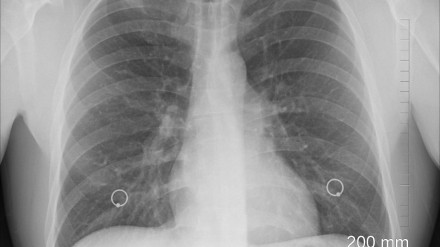

Justicia y Sanidad: debate en el IV Congreso Andaluz en Córdoba

En esta edición se abordan temas tan importantes como la falta de profesionales, la Inteligencia Artificial, nuevas leyes o las reclamaciones de los pacientes, entre otros